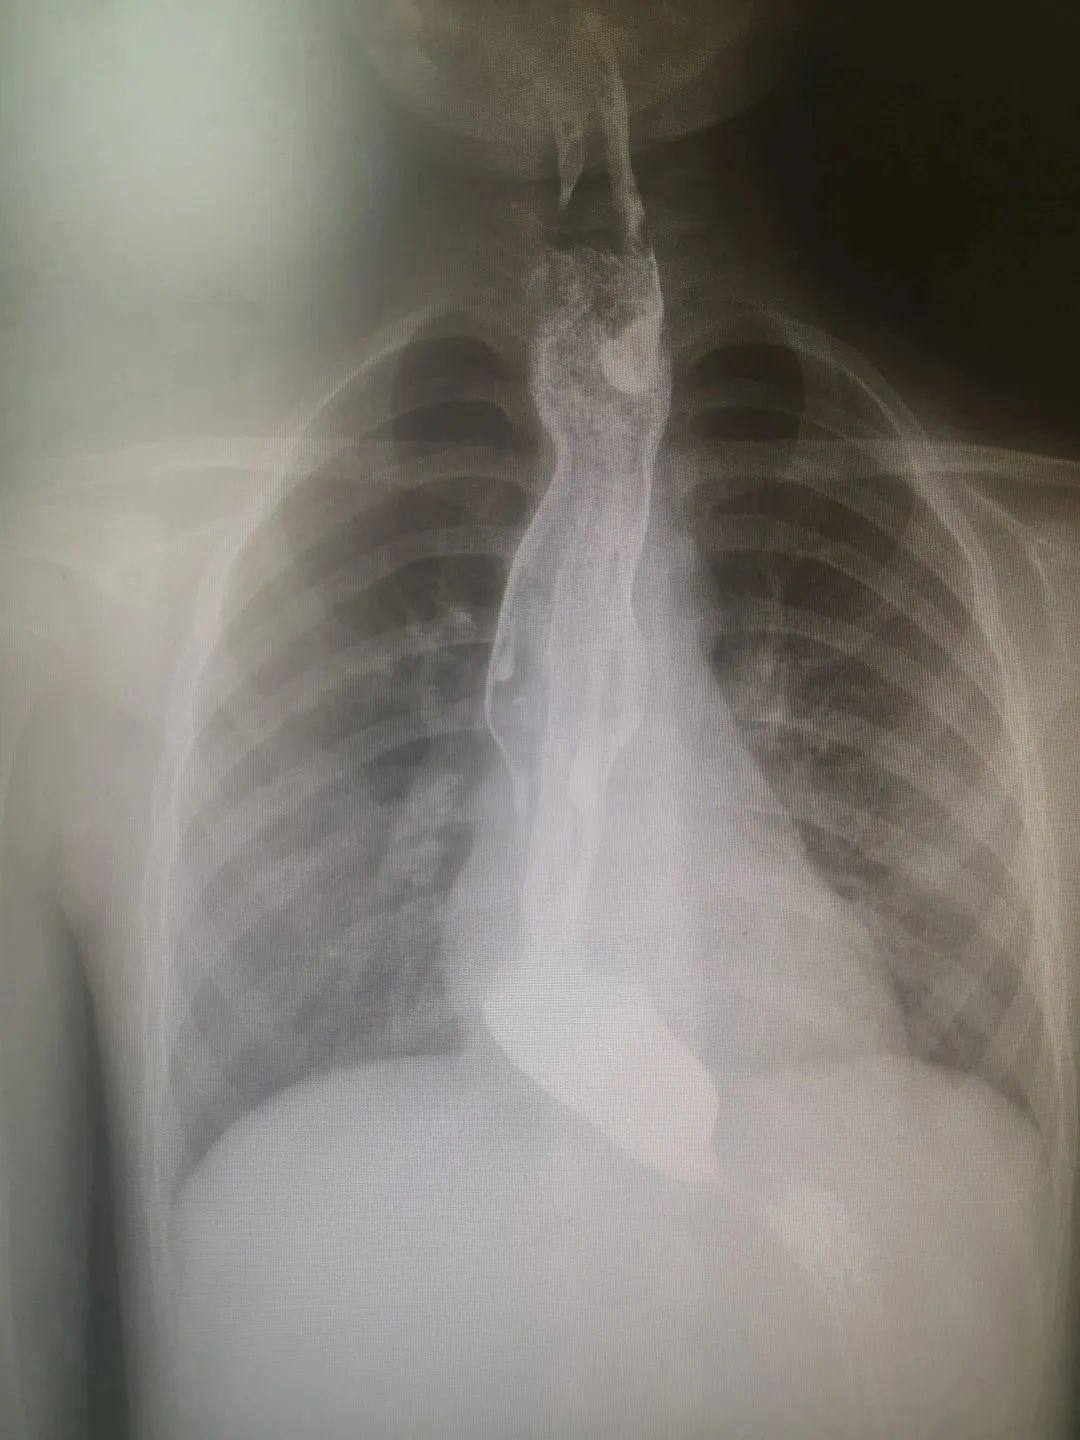

食道造影显示该患儿食道下端有鸟嘴样改变,食道下端扩张

受术6岁患儿反复呕吐2年多,至多家大医院求医治疗未果,经人介绍找到国壮小儿外科主任杨体泉。食道造影显示该患儿食道下端有鸟嘴样改变,食道下端扩张。完善相关检查后,2月20日,黄金狮教授主刀为患儿行腹腔镜下HeIIer-Dor术,该手术分两个步骤完成,首先在贲门前和食道下段将肌层切开,让痉挛的肌肉从紧缩的“O”型变为“C”型,以解决食道下端梗阻问题;然后再施行胃底叠迭术,将“C”型食管包裹,以解决食管返流问题。该手术通过肚脐自然通道以及肚脐周边3个约1cm的小孔进行,手术微创、无血,有利于患儿快速康复。